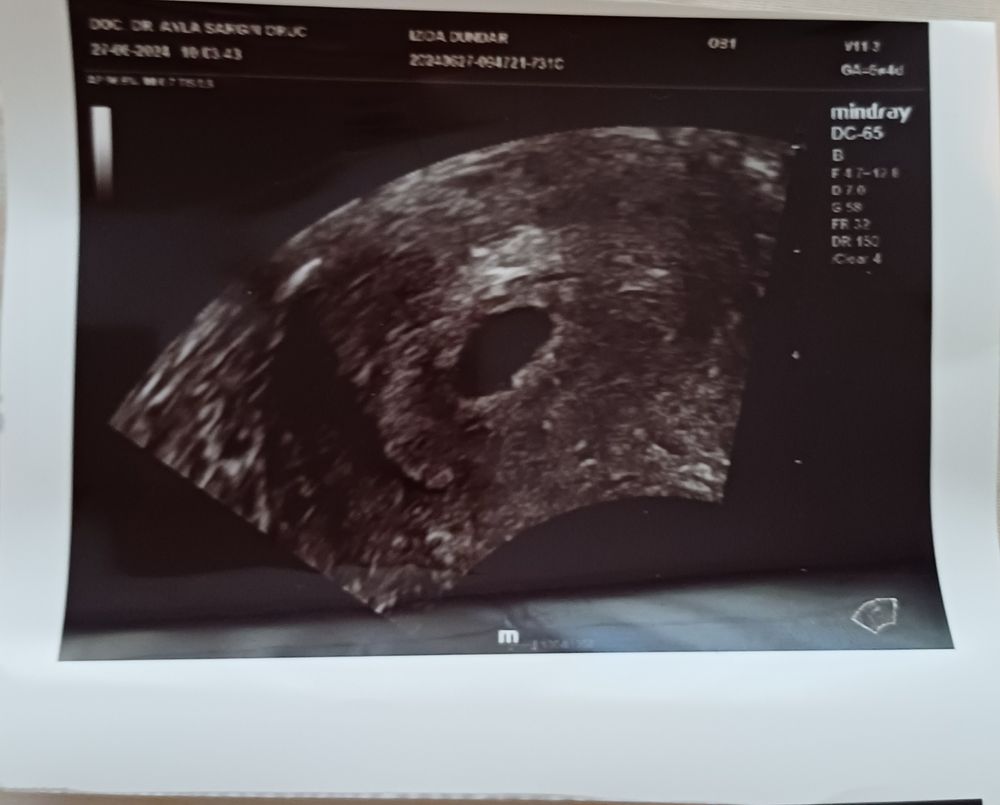

4-5 недель, ПЯ 13мм, мешочек 4мм - эмбриона было не видно. 6-7 недель, ПЯ 28мм, мешочек 6мм - эмбрион уже визуализировался, сб + Разница в узи 10 дней.

Мой эмбрион нашелся с сб в 7+2 по месячным,пя тогда было уже 21 мм,а ктр 5 мм

Denizcik , делала,на сроке 6+2.Нашли пустое пя размером 10 мм и отправили гулять неделю.Пришла через неделю и малыш уже был на месте.Ждите,шансы есть🙏